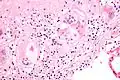

Micrografía de cuerpos de asteroides en sarcoidosis pulmonar. Tinción con hematoxilina eosina. -